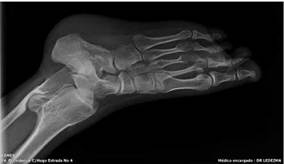

Fuente: Cortesía del Dr. Ledezma, CEMED.

Figura 1:

Proyección AP de ambas manos muestra lesiones líticas intramedulares (encondromas) radiolúcidas de márgenes definidos, con zona de transición estrecha, patrón de destrucción geográfico, que respetan la cortical sin reacción perióstica y levemente expansivas, la lesión más representativa está localizada en la tercera falange proximal de la mano izquierda, en su extremo proximal.